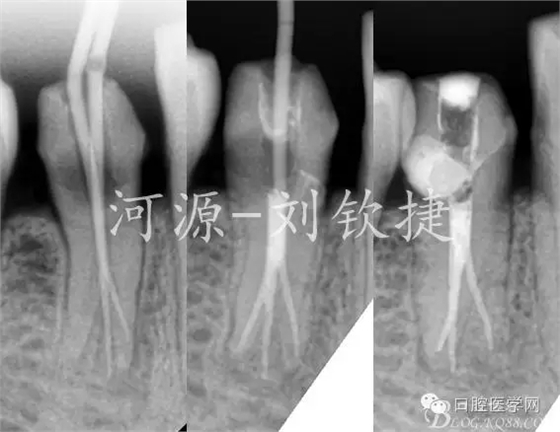

輔助檢查:X-Ray顯示44未做根管治療,根管影像在根中1/2突然消失,且明顯可見近遠根,根尖區(qū)有模糊陰影;拆除冠修復(fù)體后CBCT顯示44C型根管,頰側(cè)1根,舌側(cè)2根,頰側(cè)頸1/3白色影像達髓腔。可判斷最初就醫(yī)的原因是楔缺導(dǎo)致的牙髓炎。

由于條件不足下,在X-Ray監(jiān)測下完成根充↑